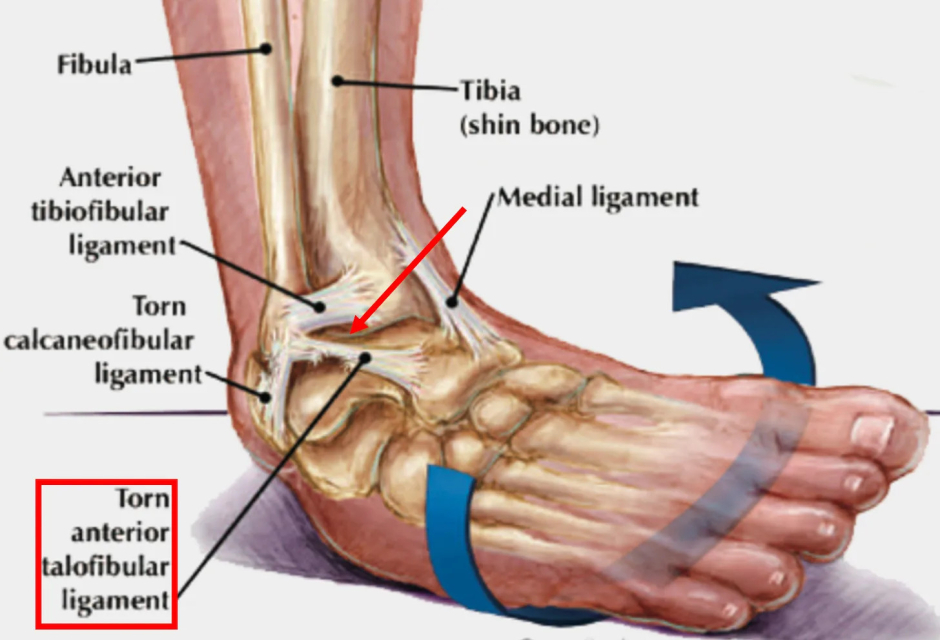

Ligamentous weakness is frequently caused by a chronic injury to a ligament (or an injury which did not properly heal). For example, when the ankle is injured from a sprain, the ligament that keeps the ankle from turning inwards gets damaged, predisposing us to an unstable ankle and future ankle injuries until the ligament is repaired and strengthened with an appropriate regenerative therapy.

This results in sprains that are treated with NSAIDs often being predisposed to future injuries (since the stability given to the joint by those ligaments is partially lost until something like a regenerative therapy is given to repair that ligament)-which in the case of ankle sprains is something I and colleagues frequently see in our patients.